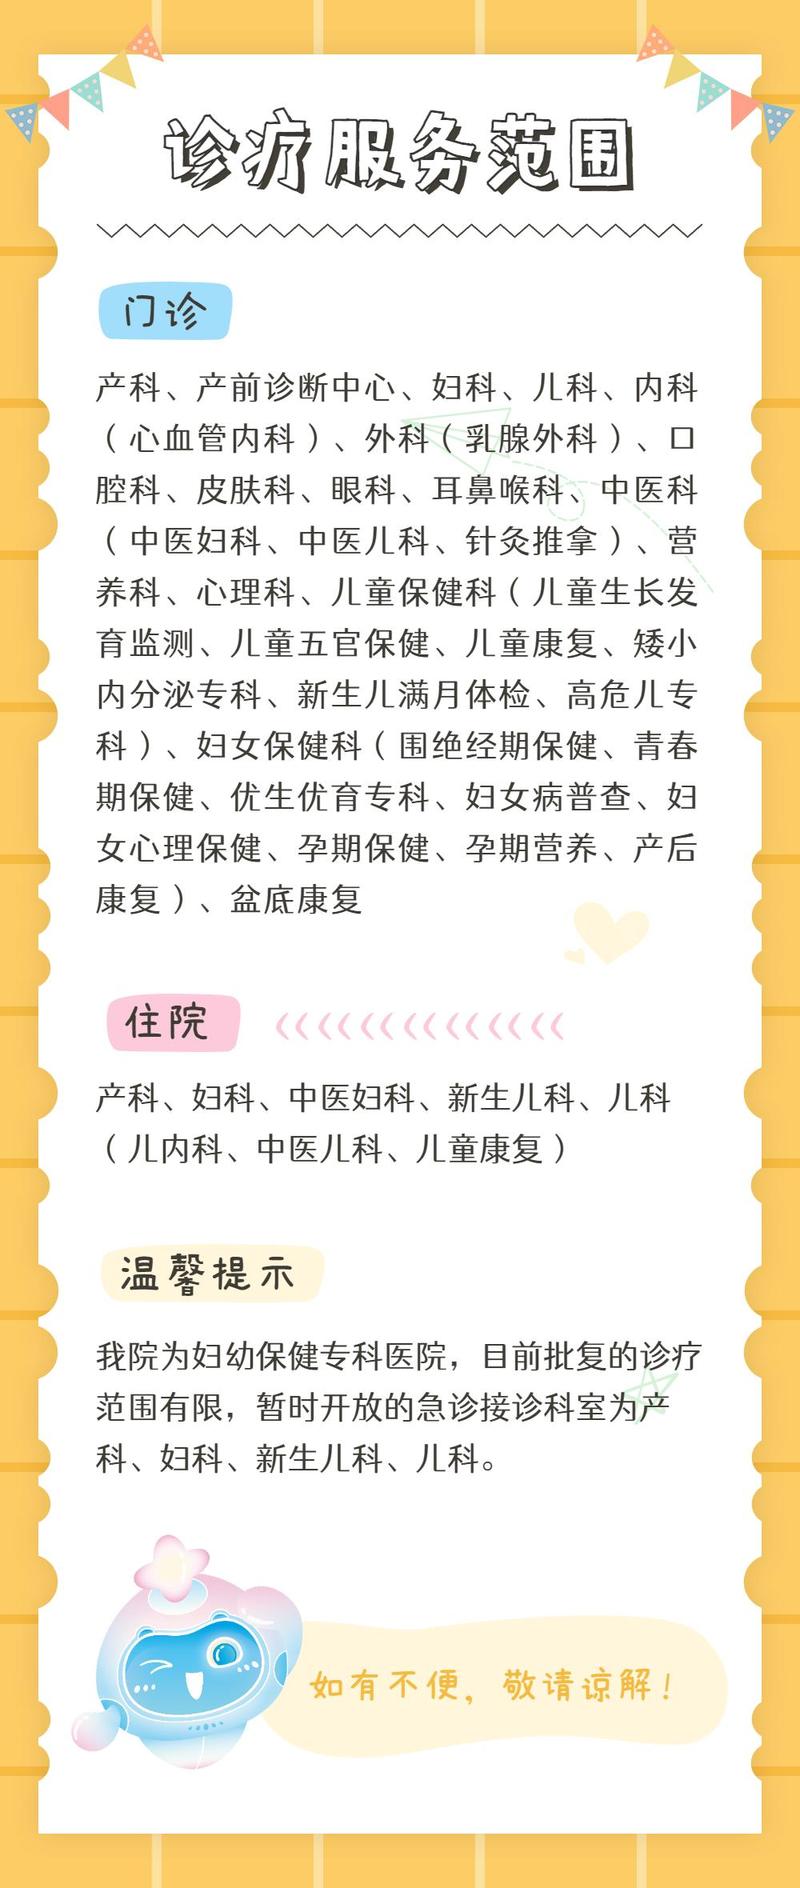

口腔科业务范围

●儿童口腔项目

开展儿童龋病(蛀牙)、牙髓根尖周病的防治、牙外伤的治疗、发育异常的防治、乳牙早失的间隙管理。开展前牙的美容修复、后牙的金属预成冠修复、氟防龋治疗及窝沟封闭等特色项目。

●口腔正畸项目

针对儿童、青少年、成人的各类牙颌畸形,包括牙列拥挤,“龅牙”,“地包天”,“开颌”等,运用各种固定、功能及活动矫治技术矫治。拥有儿童和成人隐形矫治等特色项目。

●牙体牙髓治疗项目

主要治疗成人及青少年的各种牙痛、龋病(蛀牙)、牙髓病、根尖周病、牙外伤以及牙发育性缺陷等牙体牙髓疾病。开展了各种复杂根管治疗,采用国内先进的热牙胶充填。

●牙周治疗项目

主要治疗表现为成人牙龈红肿、出血、松动、咀嚼无力、牙龈退缩等牙周疾病。开展椅旁口腔卫生指导、洁治术、根面平整术、牙龈成型术、翻瓣术、截根术、牙周植骨术、根分叉病变治疗、松牙固定术等各类规范化的牙周系统治疗。

●口腔外科项目

开展成人及儿童的牙齿拔除,拥有无痛下微创拔牙;开展牙槽骨休整,儿童唇系带休整等各种牙槽外科手术。

●口腔种植项目

拥有国际一流种植系统。在全口牙列缺失时,种植可用于单颗牙缺损或多颗牙造成牙列缺失的修复,种植体支持式覆盖义齿等。能开展为前牙行即拔即种,拔牙后种植位点保存,骨量不足时的多种植骨与上颌窦提升种植。

●口腔修复项目

主要针对成人及老年人牙齿与牙列的缺损、缺失进行修复,包括各种固定修复、活动修复、固定活动联合修复、尤其以瓷贴面和全瓷冠桥的美学修复。

向上滑动查看所有内容